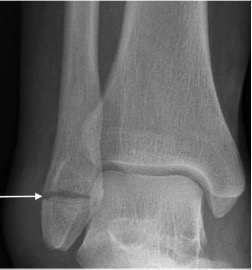

Talar neck fracture

- Impaction of talus on tibia during forced ankle dorsiflexion

- May lead to disrupted blood supply to the talar body with subsequent avascular necrosis

- The ‘Hawkin's sign' describes subchondral lucency of the talar dome 6-8 weeks after a talar neck fracture; indicates sufficient vascularity in the talus

- Absence of the Hawkins sign, seen as subchondral sclerosis may indicate disruption to the blood supply of the talar dome and underlying AVN

Hawkin’s sign with subchondral lucency of the talar dome (arrows)